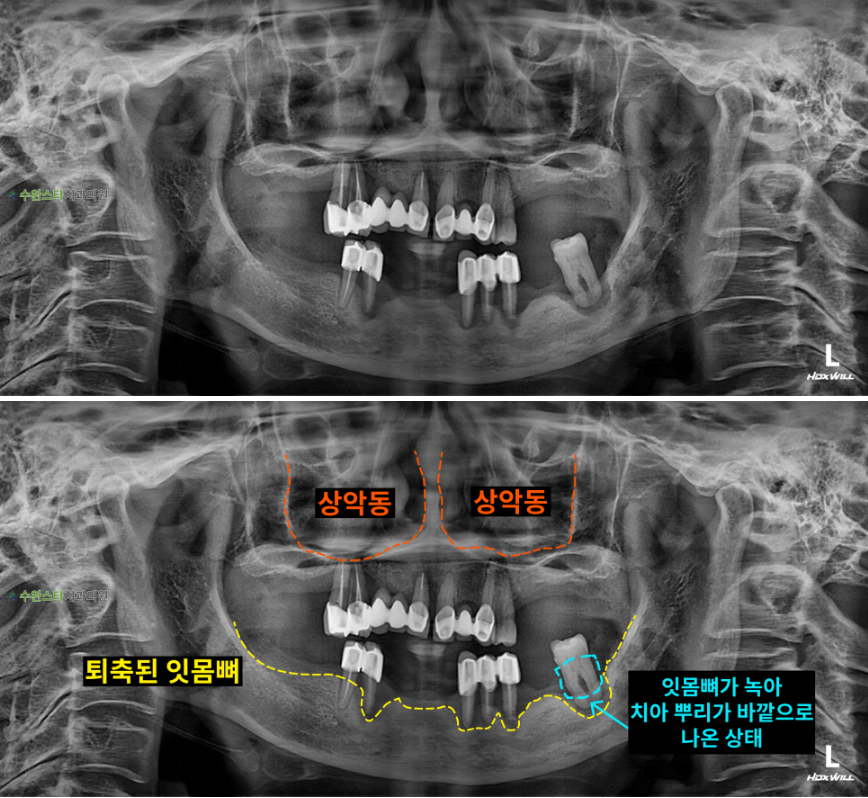

내원 시 파노라마

처음 내원 시 파노라마, 60대 여성 (2024. 12촬영)

내원 시 파노라마 사진입니다.

위 아래 잇몸뼈가

모두 많이 퇴축된 모습이라

발치 후 뼈 이식과 임플란트가

필요합니다.

이처럼 잇몸뼈가 부족한 경우에는

상악동 거상술을 통한

전체적으로 뼈이식이 필요합니다.